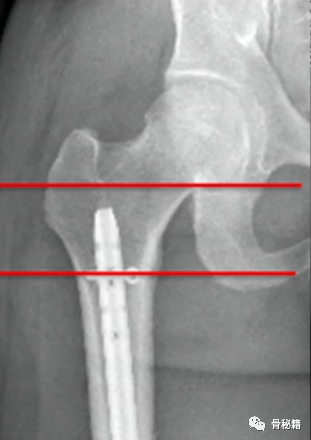

4、注意旋转。有的时候我们不太注意这个问题,有的时候中间比较粉碎,旋转容易忽略,一般来说是保持一个标准正位,近端是看小粗隆的形态,大约露出1/3-2/3,远端是看髌骨在不在两个股骨髁的中间

该例患者在复位置钉后发现远端髌骨不在股骨髁的中心,后进行旋转调整。

5、钉子的深度。逆行髓内钉的最佳深度是布鲁门萨线的顶点位置,正位居中

近端一般是小粗隆水平以上